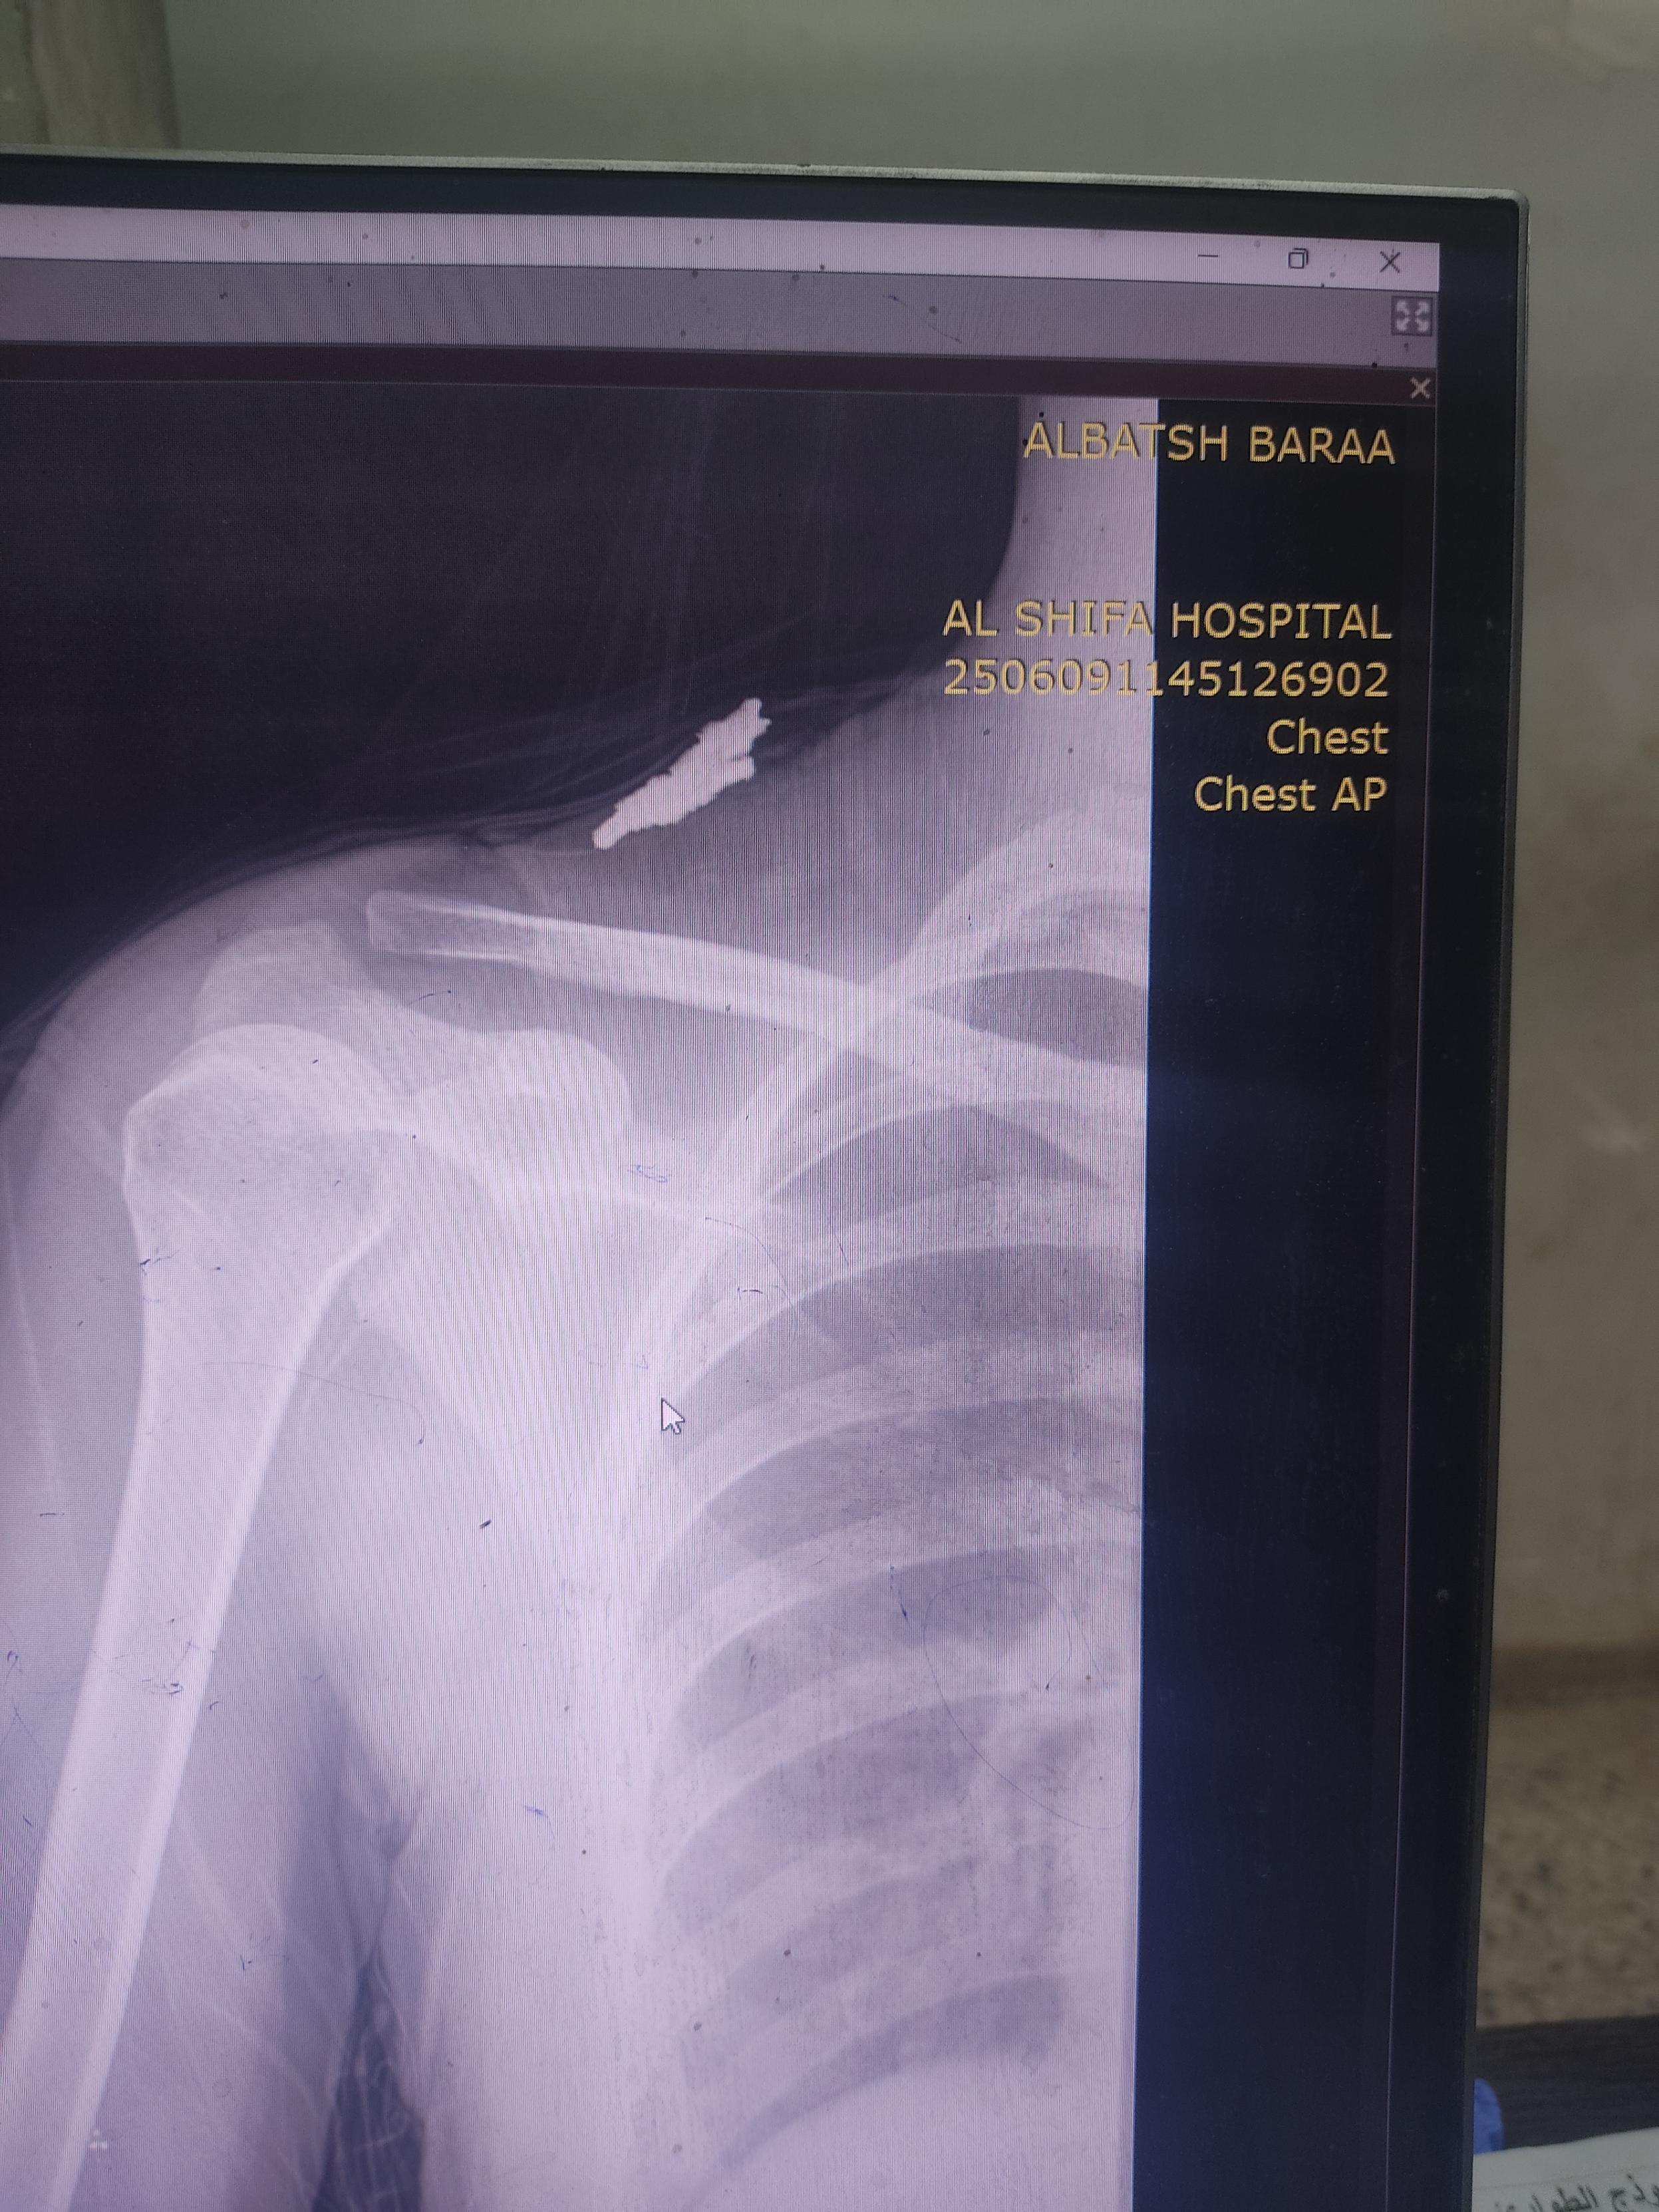

One of the stories that deeply mad me today was of a 9-year old girl who was hit by shrapnel in the shoulder. Her entire family died.Sadly, the shrapnel severed the nerves supplying her arm, which will result in complete paralysis of the limb. Unfortunately,We seeing many such handicap

2. https://cdn.masto.host/freefreeps/media_attachments/files/114/694/556/544/451/498/original/640a4c907a4074a7.jpg

3. https://cdn.masto.host/freefreeps/media_attachments/files/114/694/570/248/965/216/original/641ad459267d4d02.jpg